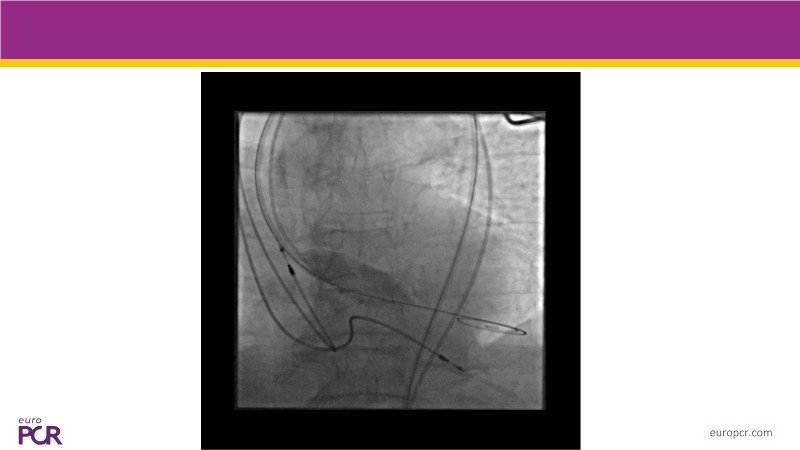

This session explores some of the most clinically complex scenarios encountered in TAVI practice. Three real-world cases address key challenges such as intervention sequencing and transcatheter valve selection in patients with combined coronary artery disease and severe aortic stenosis. The session also examines coronary obstruction risk assessment and protection strategies during redo TAVI, and discusses specific implantation techniques for anatomically complex cases, including large aortic valve anatomy.

- To appreciate the impact of device choice and implantation technique on coronary access and REDO TAVI

- To learn how to tailor your TAVI technique to complex clinical scenarios